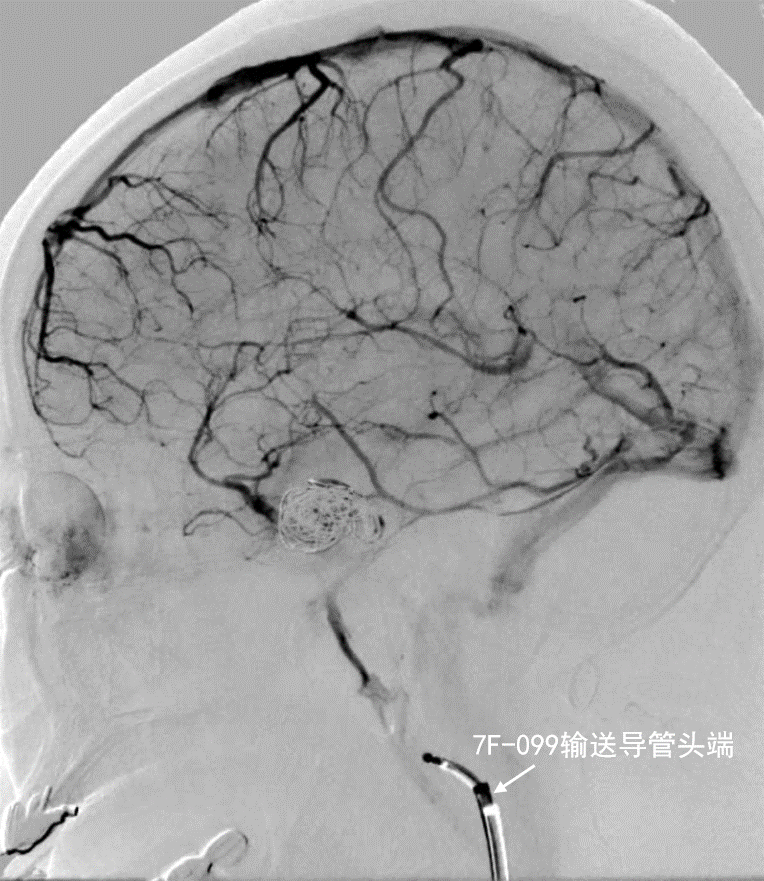

- 术后造影证实动脉瘤达大部分栓塞,载瘤动脉通畅

深瑞达7F输送导管正位造影

深瑞达7F输送导管侧位造影